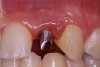

Before the day of surgery, the patient was seen by the orthodontist for the removal of the orthodontic brackets. The patient still was not pleased with the position of the two centrals, and it was determined that this would be addressed after implant placement (Figure 13A). The anatomical variations of the crestal tissue and lack of interdental papilla can be appreciated in the close-up views of the right and left sites (Figure 13B and 13C). There were no surprises on the day of surgery as all of the decisions were made during the planning phase, before the scalpel ever touched the patient. The occlusal view of the CT 3D model revealed the wider alveolar ridge on the right side and thinner crest on the left side (Figure 14A). This was confirmed when the full thickness mucoperiosteal flaps were elevated, and the underyling bone revealed (Figure 14B). The tooth-borne templates were designed to facilitate the drills and drilling sequence specific to the diameters of the predetermined implants (Figure 15A). Each template contained an embedded 5-mm long stainless steel tube, which was approximately 0.2-mm wider than each drill (just wide enough to allow for the drills to rotate freely). Once positioned over the natural teeth, the template was secure and offered precision accuracy in transferring the implant locations from the original software-designed plan, allowing the potential for internal and external irrigation (Figure 15B). The 3.7-mm diameter Tapered Screw-Vent implant drilling sequence requires three drills: pilot, intermediate, and final sizing. Thus, three separate templates were fabricated to a.commodate these sizes. The templates were removed easily and replaced with the next sequential size in less time than it takes to change the drill on the surgical handpiece. After the osteotomies had been.completed, the implants were delivered to the site (Figure 16A and Figure 16B). For this internal hex connection implant, the author r.commends that the flat of the antirotational hex be positioned to the facial for proper orientation of the restorative.components (Figure 17A). Preprepared margins were created from a milled titanium fixture mount transfer post, which was delivered to the implant as support for an immediate transitional restoration. The facial “dot” helped confirm the orientation of the abutment to the facially positioned flat side of the internal hex connection (Figure 17B). Before cementation of the transitional acrylic restorations, a closed-tray, fixture-level impression was made, and a soft-tissue model fabricated.

Figure 13a  Before implant surgery, the orthodontic brackets were removed, revealing (A) the position of the centrals, and (B, C) the anatomical variations of the crestal tissue and lack of interdental papilla.

Figure 13a

Figure 13b  Before implant surgery, the orthodontic brackets were removed, revealing (A) the position of the centrals, and (B, C) the anatomical variations of the crestal tissue and lack of interdental papilla.

Figure 13b

Figure 13c  Before implant surgery, the orthodontic brackets were removed, revealing (A) the position of the centrals, and (B, C) the anatomical variations of the crestal tissue and lack of interdental papilla.

Figure 13c